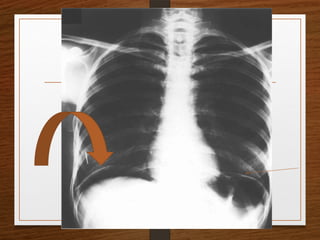

What are the important causes of

cannon ball shadows in chest X-ray?

• Metastasis

• Benign lesion

 Fungal infection—Histoplasmosis, coccidioodomycosis,

aspergillosis.

 Parasitic infection—Filarial infection, hydatid disease.

 Sarcoidosis.

 Wegener’s granulomatosis.

 Rheumatoid nodules.

What are theimportant causes of cannon ball shadows in chest X-ray? • Metastasis • Benign lesion  Fungal infection—Histoplasmosis, coccidioodomycosis, aspergillosis.  Parasitic infection—Filarial infection, hydatid disease.  Sarcoidosis.  Wegener’s granulomatosis.  Rheumatoid nodules.